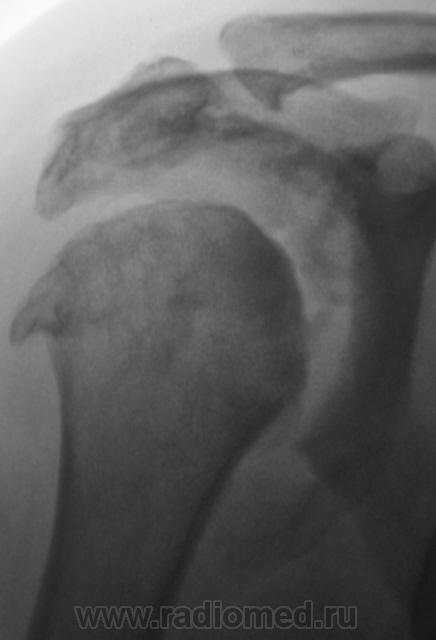

Где же подевался плечевой отросток лопатки? Что за мягкотканный компонент в подмышечной области? Костные разрастания само собой...это видно...

Если бы и конгруэнтность суставной поверхности плечевой кости была бы нарушена - предположил бы сирингомиелию...пока в раздумии, задачка не из простых....